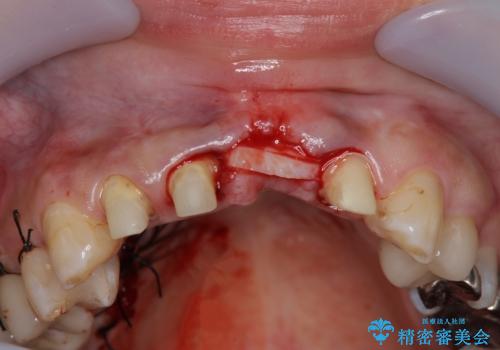

左側の前歯には他院で埋入されたポジションの悪いインプラント補綴により歯冠長の長いクラウンが装着されており、感染による排膿も認められこのまま審美性を改善するのは難しい状態です。

不良インプラントを除去し最終的にブリッジによる補綴で審美性の改善を行うこと、その準備として骨の造成・歯肉の移植による歯の欠損部顎堤のボリュームを維持・増大を計画します。

感染したインプラントからは排膿が間欠的に認められ、掻爬・除去が検討されうるような状況でした。

より審美的な改善を強く求められたため、インプラントを除去し可及的に欠損部顎堤を増大したのちブリッジによる審美改善を行いました。